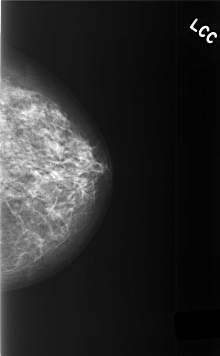

C_0471_1.LEFT_CC

LEFT_CC LINES 5696 PIXELS_PER_LINE 3520 BITS_PER_PIXEL 12 RESOLUTION 50 NON_OVERLAY